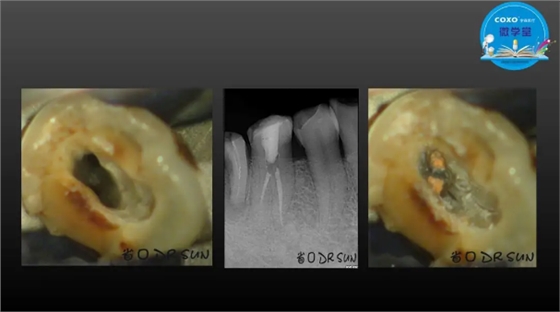

主任医师,牙体牙髓副主任, 广东省口腔医院牙体牙髓科 主任医师。2003年硕士研究生毕业,研究方向为牙体牙髓病学,擅长于牙体牙髓病的诊断、龋齿、牙髓炎、根尖周病的治疗以及前牙美容修复。